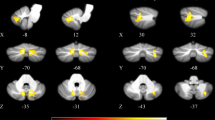

Investigating the impact of dopaminergic treatment to general connectivity in PD patients, we observed a significant EC increase in cerebellum and brainstem with a pairwise comparison of the EC maps in the OFF and the ON condition. Figure 1 shows the significant result (p < 0.05 with FWE correction at the cluster level) using the maximum intensity projection (glass brain view). Note that we did not find any significant treatment-related EC decrease.

General connectivity increase in cerebellum and brainstem after levodopa in PD patients (N = 24) compared to OFF condition. Result based on eigenvector centrality analysis of resting-state fMRI restricted by a mask involving expanded primary motor, premotor, sensorimotor cortex, basal ganglia, thalamus, brainstem, and cerebellum (blue region). Gray cluster shows the pairwise ON vs. OFF difference (p < 0.05 with family-wise error correction at the cluster level)

Table 2 presents a list of all local maxima of T scores within the cluster of general connectivity increase in cerebellar brain regions and brainstem after dopaminergic treatment. EC increase was obtained in the anterior and posterior lobe of the left and right cerebellum and particularly in lobuli V, VI, VIIIa, and IX. In the brainstem, local maxima were found in the pons and in the tegmentum. Figure 2 also shows this EC increase with orthogonal brain sections for several selected maxima (see first and fourth row, color-coded in red/yellow). The same EC increase was also obtained with the nonparametric approach and the TFCE toolbox with 10,000 permutations. Figure 3 shows a direct comparison between analyses (p < 0.05 with FWE-correction at the cluster level). All 16 local maxima obtained with the parametric analysis (see Table 2) were also found to be significant with the nonparametric analysis.

Resting-state fMRI connectivity increase of general and selective connectivity in PD patients (N = 24) in the ON compared to the OFF condition. The general connectivity increase (eigenvector centrality analysis; contrast ON vs. OFF condition) in cerebellum and brainstem are shown in the first and the fourth row of images (red-yellow clusters). The selective connectivity increase (correlation analysis; contrast ON vs. OFF condition) between eight seed voxels and extra-cerebellar brain structures are shown in rows 2 and 3 and in rows 5 and 6 (rainbow color clusters). The columns are sorted with respect to the z coordinate of each seed voxel displayed as color spheres on the general connectivity maps. Seed voxel locations and positions of the coronal and axial slices are shown using the coordinates in the MNI space. Color-coded clusters show areas with connectivity increase in the ON as compared to the OFF condition. All analyses were restricted by mask shown on Fig. 1; however, results of all seed-based correlations were also significant in full-brain analyses including family-wise error (FWE) correction at the whole-brain level (p < 0.05 at the cluster level). C connectivity, GP globus pallidus, Pu putamen, SM1 primary sensorimotor cortex, SN substantia nigra, STh subthalamus, RN red nucleus, Th thalamus

Resting-state fMRI connectivity increase of general connectivity in PD patients (N = 24) in the ON compared to the OFF condition. The general connectivity increase (eigenvector centrality analysis; contrast ON vs. OFF condition) in cerebellum and brainstem are shown with both parametric and nonparametric analysis (red-yellow clusters). Nonparametric analysis was performed using the threshold-free cluster enhancement (TFCE) technique with 10,000 permutations and a significance level of p < 0.05 (family-wise error corrected). Interestingly, the same result was obtained with both approaches. Note that all 16 local maxima obtained with the parametric analysis (see Table 2) were also detected as significant in the nonparametric analysis. A analysis, EC Eigenvector centrality